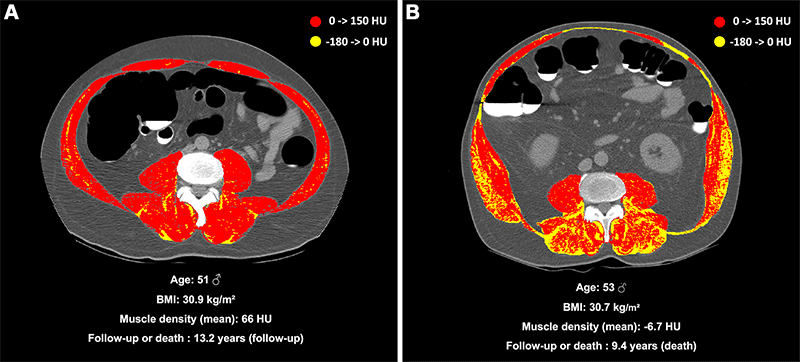

(A) Unenhanced axial abdominal CT image with a Hounsfield unit–based color scale of skeletal muscles in a 51-year-old man with obesity, smoking history, no type 2 diabetes, and no history of cardiovascular events at inclusion shows mild fatty infiltration in the muscles (myosteatosis, yellow), with most voxels in the positive range of Hounsfield units (red). The patient was lost to follow-up after 13.2 years. (B) Unenhanced axial abdominal CT image with a Hounsfield unit–based color scale of skeletal muscles in a 53-year-old man with obesity, smoking history, no type 2 diabetes, and no history of cardiovascular events at inclusion shows severe fatty infiltration in the muscles (myosteatosis, yellow), mostly distributed in the paravertebral (ie, erector spinae and multifidus) and oblique muscle groups. The patient died after 9.4 years of follow-up. BMI = body mass index.